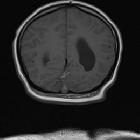

Cerebellar

abscess secondary to occipital dermoid cyst with dermal sinus. Post-contrast coronal T1W images showed ring enhancement around focal collection.